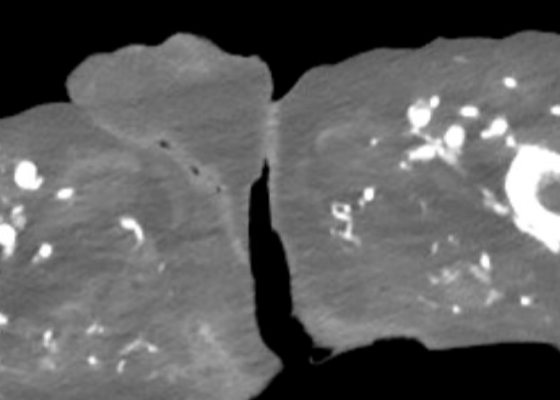

DOI: https://doi.org/10.5070/M5.52203A computed tomography (CT) scan of the abdomen and pelvis was significant for scrotal fluid and punctate gas locules (red arrow) without discrete evidence of invasion into the adjacent soft tissues, suspicious for Fournier’s gangrene. There was also fluid collection centered around the seminal vesicles suggestive of an abscess.